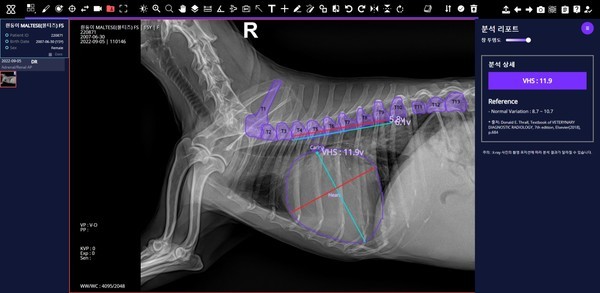

▲ 오이세 스카이동물메디컬센터 원장이 진료실에서 ‘엑스칼리버’를 통해 분석한 반려견의 엑스레이 사진을 설명하고 있다. 사진= SK텔레콤. |

질환탐지율도 상당히 높다는 게 SK텔레콤의 설명이다. 반려견 근골격 이상 영역 7종 검출모델 평균 질환탐지율은 86%, 반려견 흉부 이상 패턴 10종 분류모델 평균 질환탐지률은 84%에 달했다. 반려견 심장크기측정(VHS) 측정의 경우, 정확도가 97%나 됐다. 관계자는 데일리임팩트에 “AI의 질환탐지율은 분야별로 84~97% 수준에 달한다”며 ”학습데이터가 늘어날수록 AI 성능이 향상되므로, 엑스칼리버의 품질도 올라갈 것으로 본다”고 전했다. 이와 관련, 제주대가 최근 엑스칼리버 개발에 합류했다.

| ▲ 엑스칼리버를 통해 분석한 반려견의 근골격·흉부·VHS 엑스레이. 사진= SK텔레콤. |